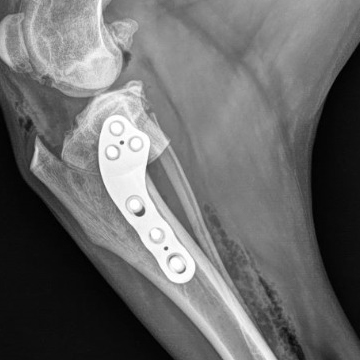

Tibial Plateau Leveling Osteotomy

This course is designed for veterinarians who want to specialize in orthopedic surgery and want to learn advanced techniques for managing knee injuries in small animals.